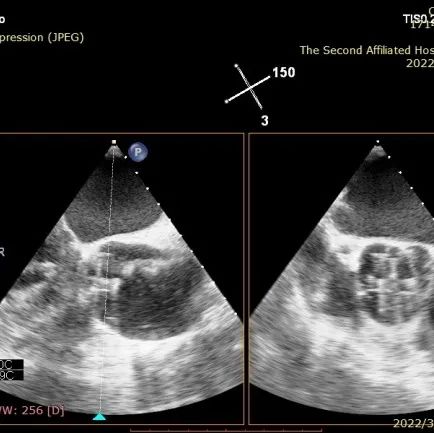

DSA和TEE显示无瓣周漏,瓣膜位置、形态良好

DSA和TEE显示J-Valve瓣架形态、位置良好,瓣叶开放活动度正常,收缩期前向血流通畅。术后一天患者精神状态良好。